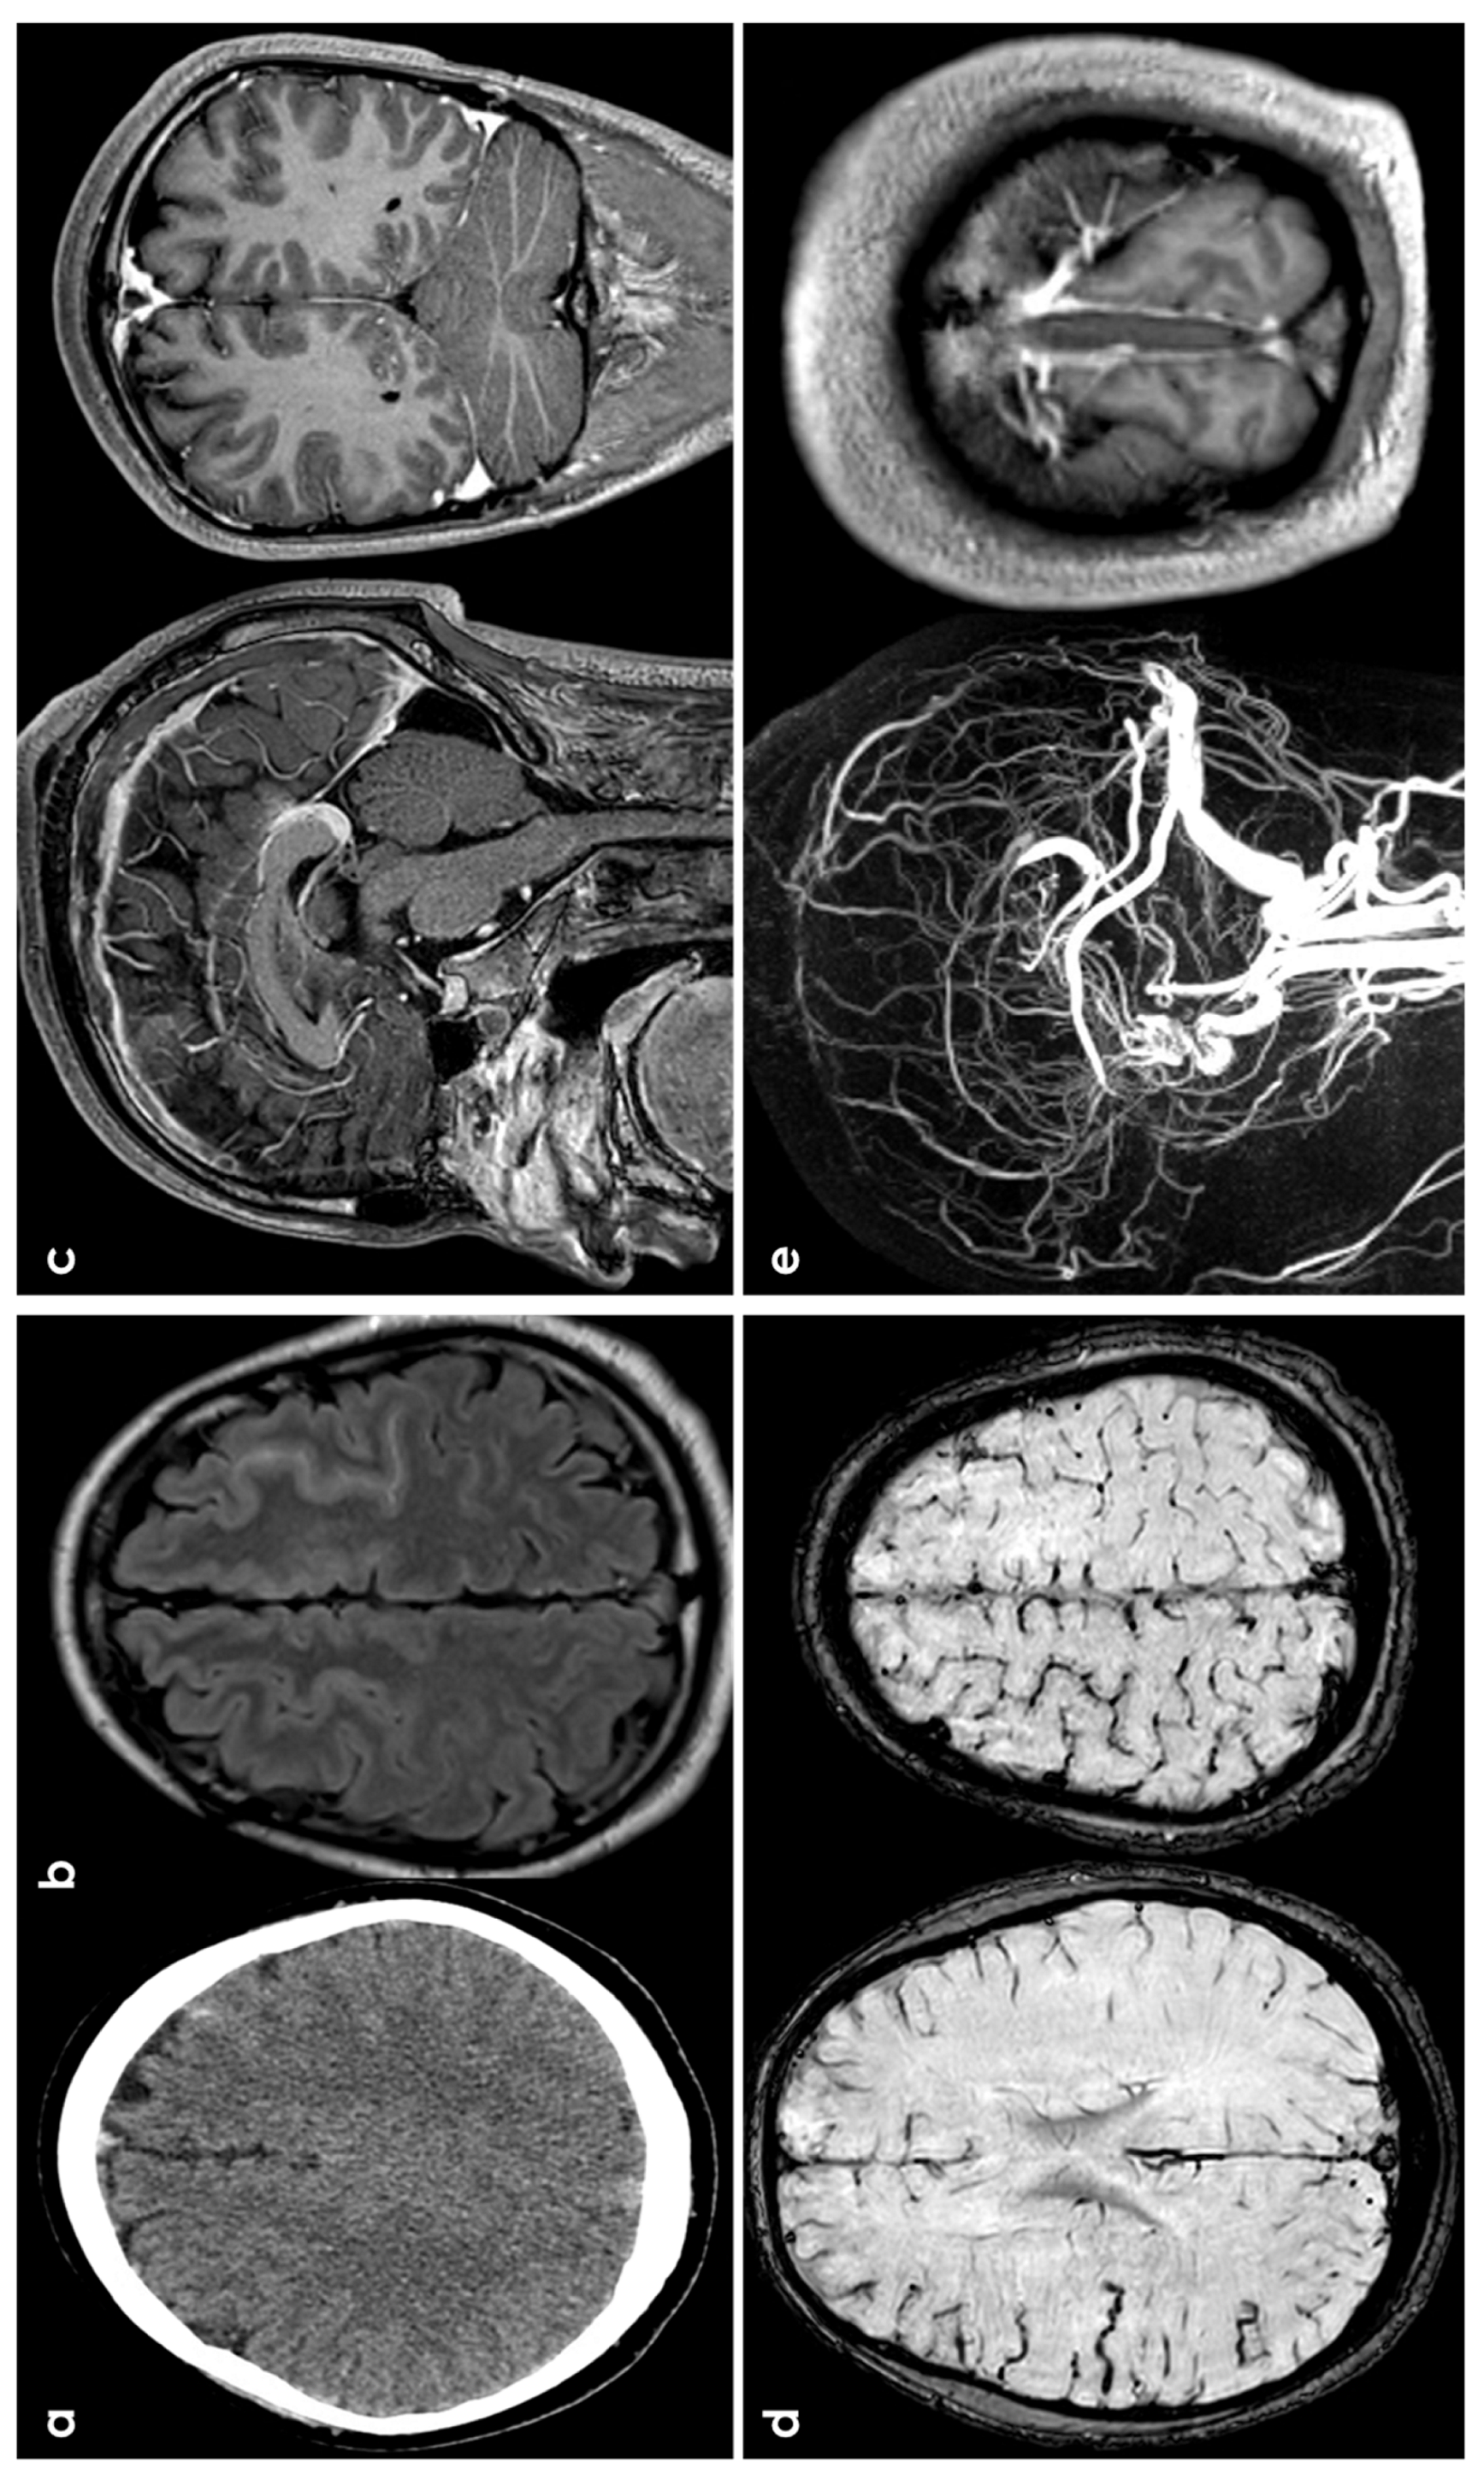

2. Epidemiology and Clinical Presentation

3.5. Primary Central Nervous System Angiitis

3.6. PRES/RCVS

3.7. Vascular Malformations